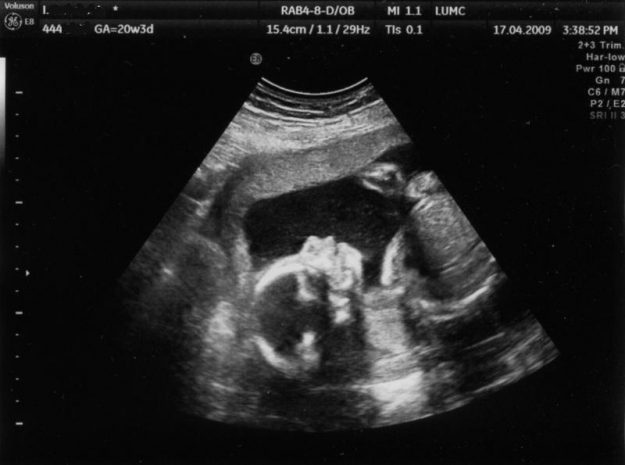

Пренаталните скрининг-тестови се група на тестови, кои му даваат информации на докторот во каква состојба се наоѓа бремената жена и нејзиното бебе. Со помош на Приска-системот, употребувајќи тест-алгоритми и ризик фактори, се генерираат различни калкулации на ризик за добивање на комплетен извештај за точна проценка на високоризични бремености. Ова се многу важни информации за докторот…